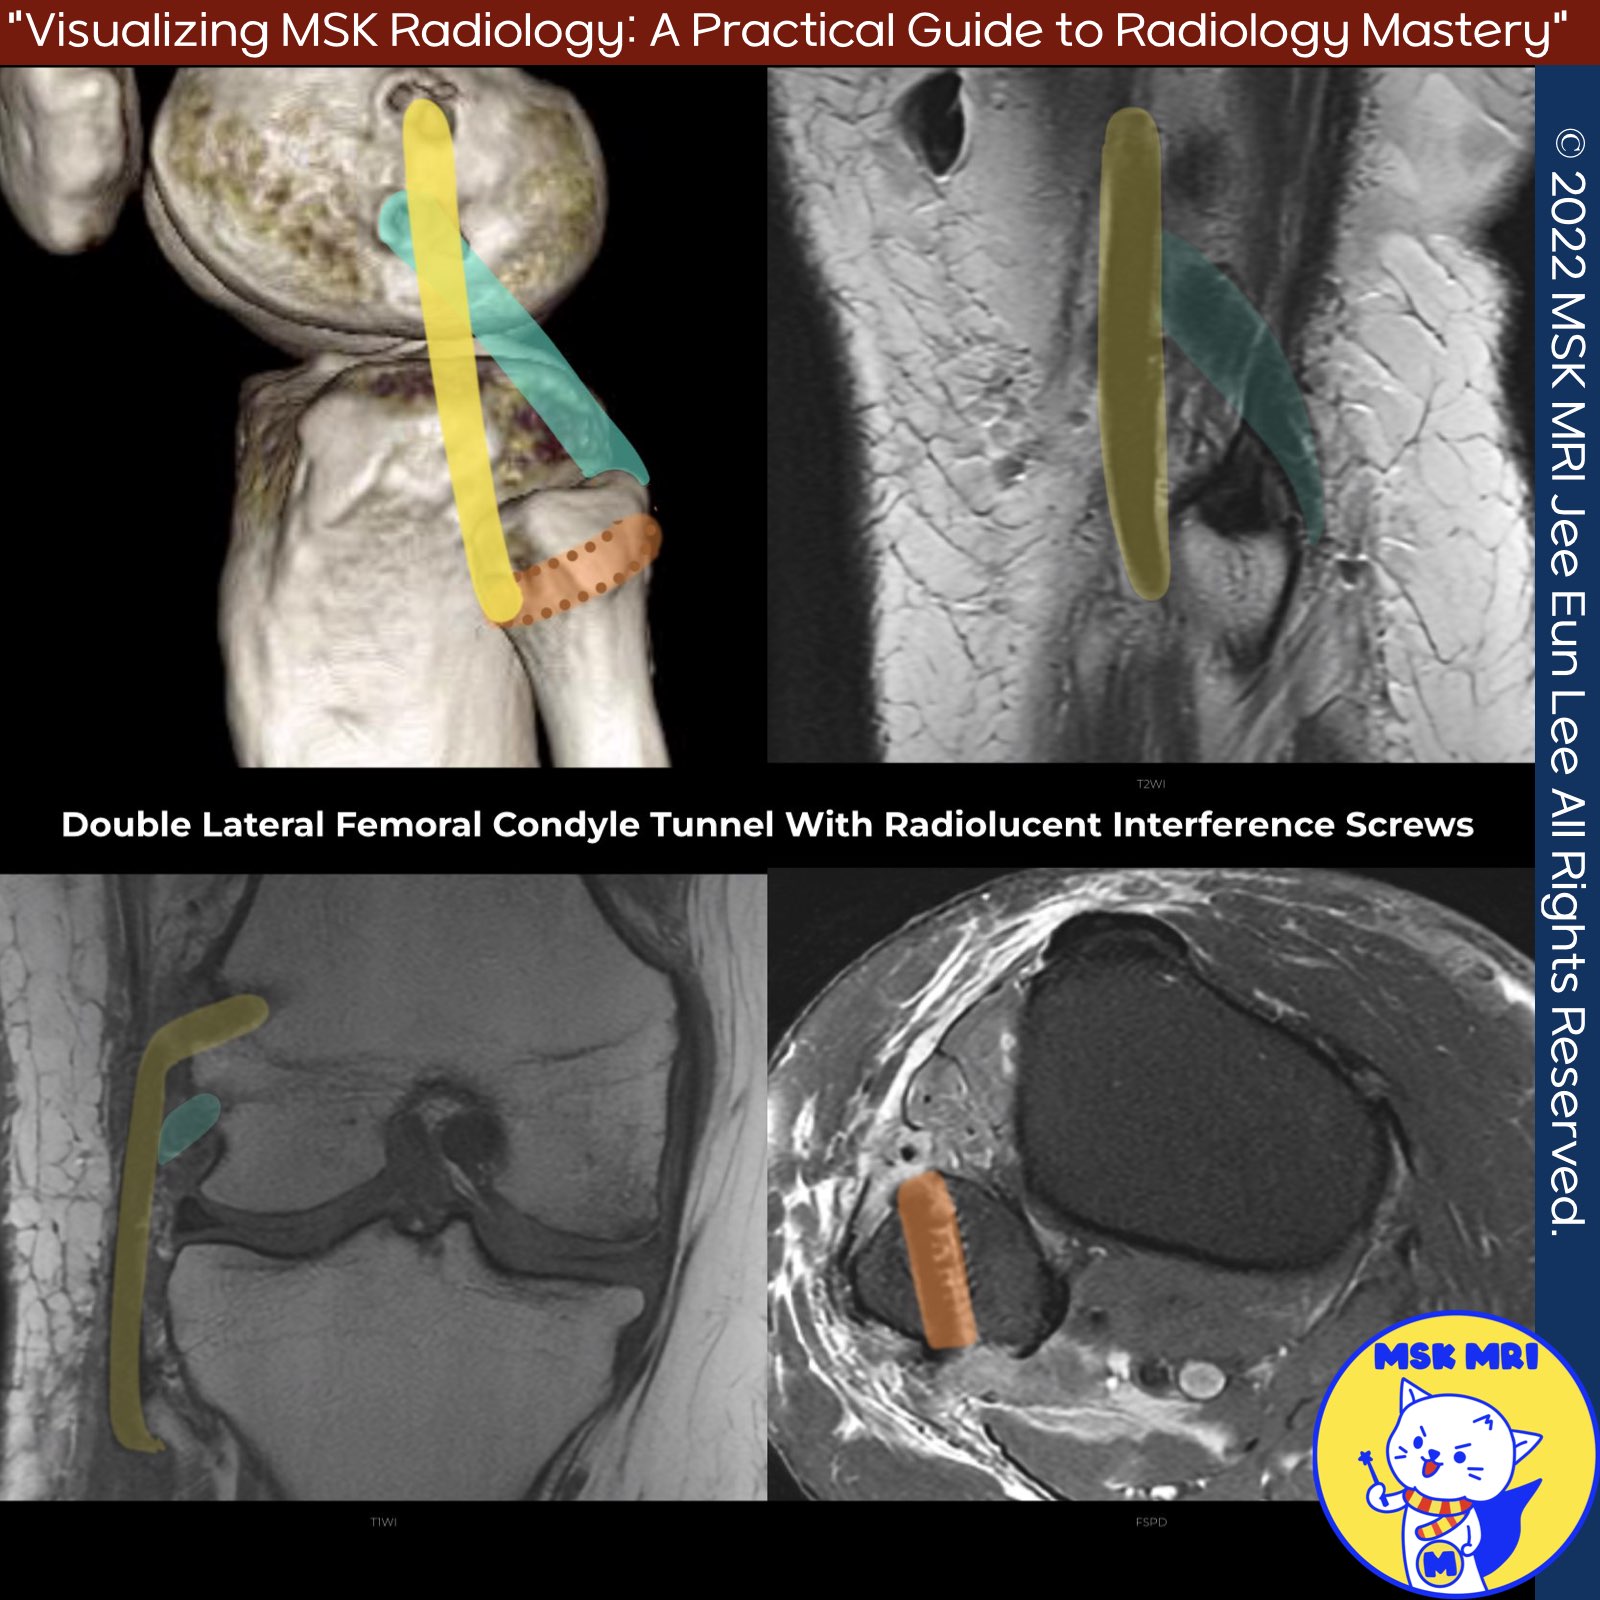

✅ Nonanatomical: These techniques do not place tunnels at the native ligament footprints.

- Larson Procedure: Uses a vertical graft limb from the fibular head to the lateral femoral condyle and an oblique graft limb from the posterior fibular head to the femoral condyle.

- Modified Larson (Arciero): Involves two femoral drill holes to reconstruct the PT and LCL footprints.

- LaPrade’s Technique: Reconstruction of the LCL, PT, and PFL with two femoral tunnels, one tibial tunnel, and one fibular tunnel. Preferred graft is a split Achilles allograft.